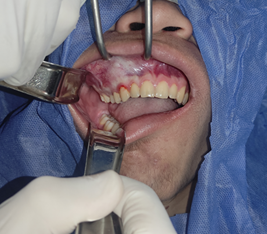

Luego de esperar el periodo de latencia del anestésico (3min), se colocó el campo abierto sobre el área de trabajo para proceder con la siguiente fase, una vez confirmada la anestesia en la zona se procede a la incisión con hoja de bisturí n°15 colocada en un mango n°3, se realizó un colgajo sulcular desde la UD 17 hasta la cara mesial de la UD 13 donde se realizó la descarga en dirección al fondo del surco, luego se realizó levantamiento del colgajo de espesor total con el periostótomo Molt #9. Esto se muestra en la figura 7.

Figura 7. Levantamiento de colgajo mucoperióstico con Molt #9 usando separadores de Branemarck y Minnesota.

Fuente: Historia Clínica Postgrado Cirugía bucal ULAC-IDOLA Julio 2021

Una vez expuesta la superficie del hueso, se procede a realizar las líneas guía con pieza de mano de alta velocidad y fresa quirúrgica 702, tomando en consideración las mediciones de trabajo obtenidas mediante el cone beam realizadas por la residente y el Adjunto Cirujano Maxilofacial, detalladas en la historia clínica del paciente en el postgrado de Cirugía Bucal ULAC-IDOLA. (Figura 8) (Tabla 1)

Figura 8. Tallado de guías para el desgaste del tejido displásico usando pieza de mano de baja velocidad y fresa tipo pimpollo.